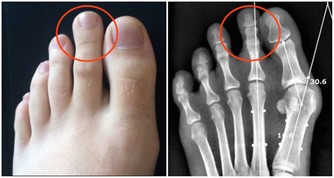

腹股溝疝,腹壁切口疝和臍疝。